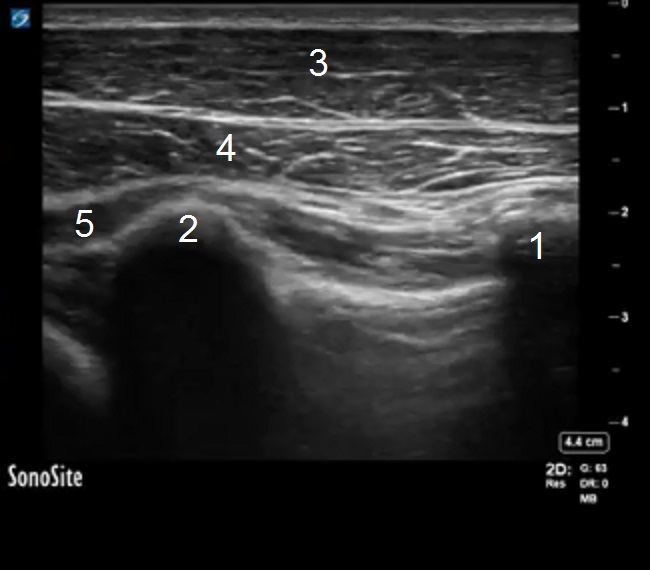

PECS Anatomy 2 Image

1. Third Rib

2. Fourth Rib

3. Pectoralis Major Muscle

4. Pectoralis Minor Muscle

5. Serratus Anterior Muscle